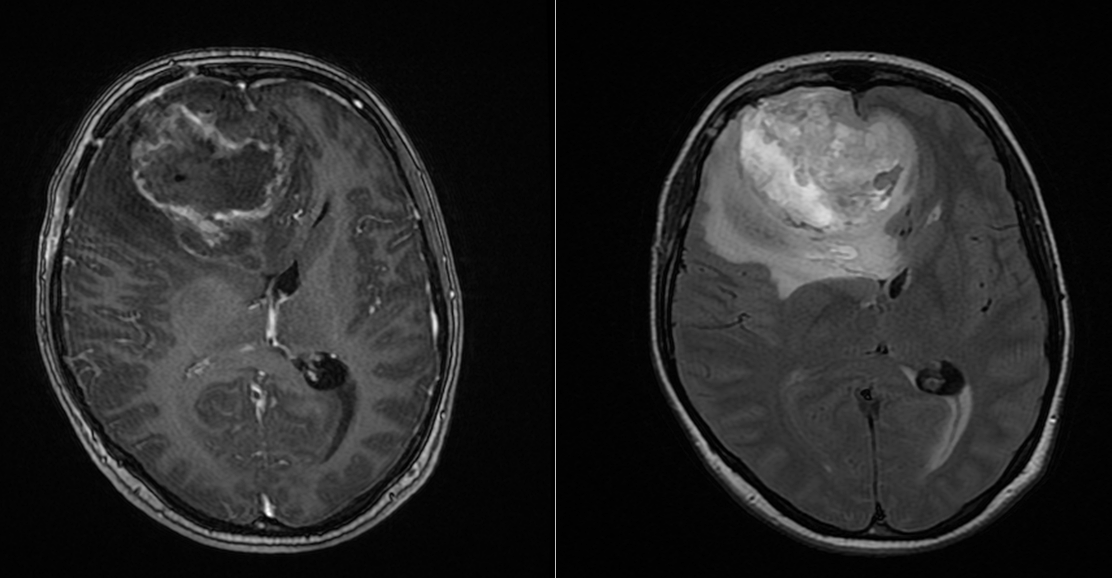

Recidiva – inevitabilitate biologică

Recidiva nu este o eventualitate, ci o etapă a evoluției bolii.

Aceasta apare de obicei:

- în vecinătatea cavității de rezecție

- rar, la distanță

La momentul recidivei, tumora este adesea:

- mai rezistentă

- mai heterogenă

- mai dificil de tratat

Opțiunile includ:

- reintervenție

- reiradiere

- chimioterapie alternativă

- studii clinice

Decizia este profund individualizată și trebuie adaptată contextului pacientului.